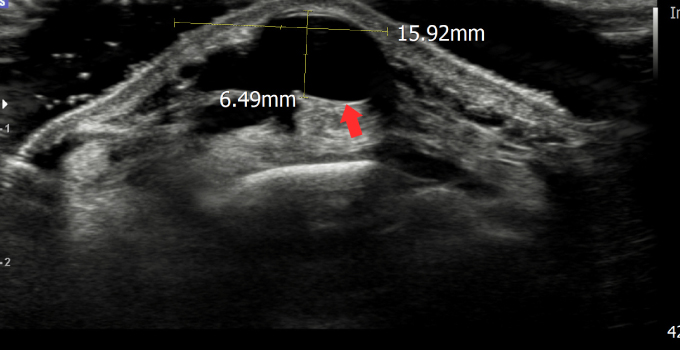

결절종

수부에 발생하는 가장 흔한 종양으로 손목의 관절을 둘러싸고 있는 얇은 성유성 피막 안에 투명하고 끈적이는 액체를 함유하고 있는 물혹성 종양입니다.

결절종 초음파 영상 사진